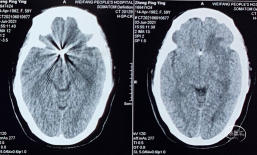

术前影像学检查

术前颅脑CT:左基底节脑出血